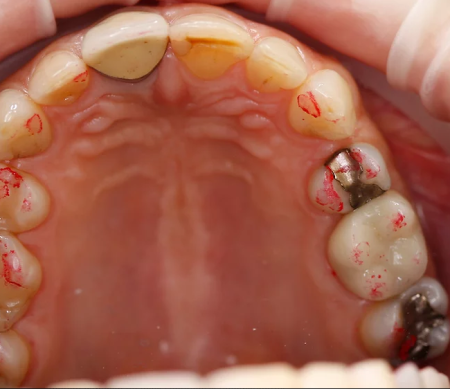

Артикуляционная бумага 40µ, красный цвет

Окклюзионная бумага толщиной 40μ особенно хорошо подходит для двухцветной демонстрации статической и динамической окклюзии. Для этого на первом этапе окрашиваются в красный цвет все контактные пункты в положении центральной окклюзии, а затем проводится второй этап с окраской динамических контактных пунктов в синий цвет. Использование синей бумаги на первом этапе и красной бумаги на втором этапе также даёт хорошие результаты.